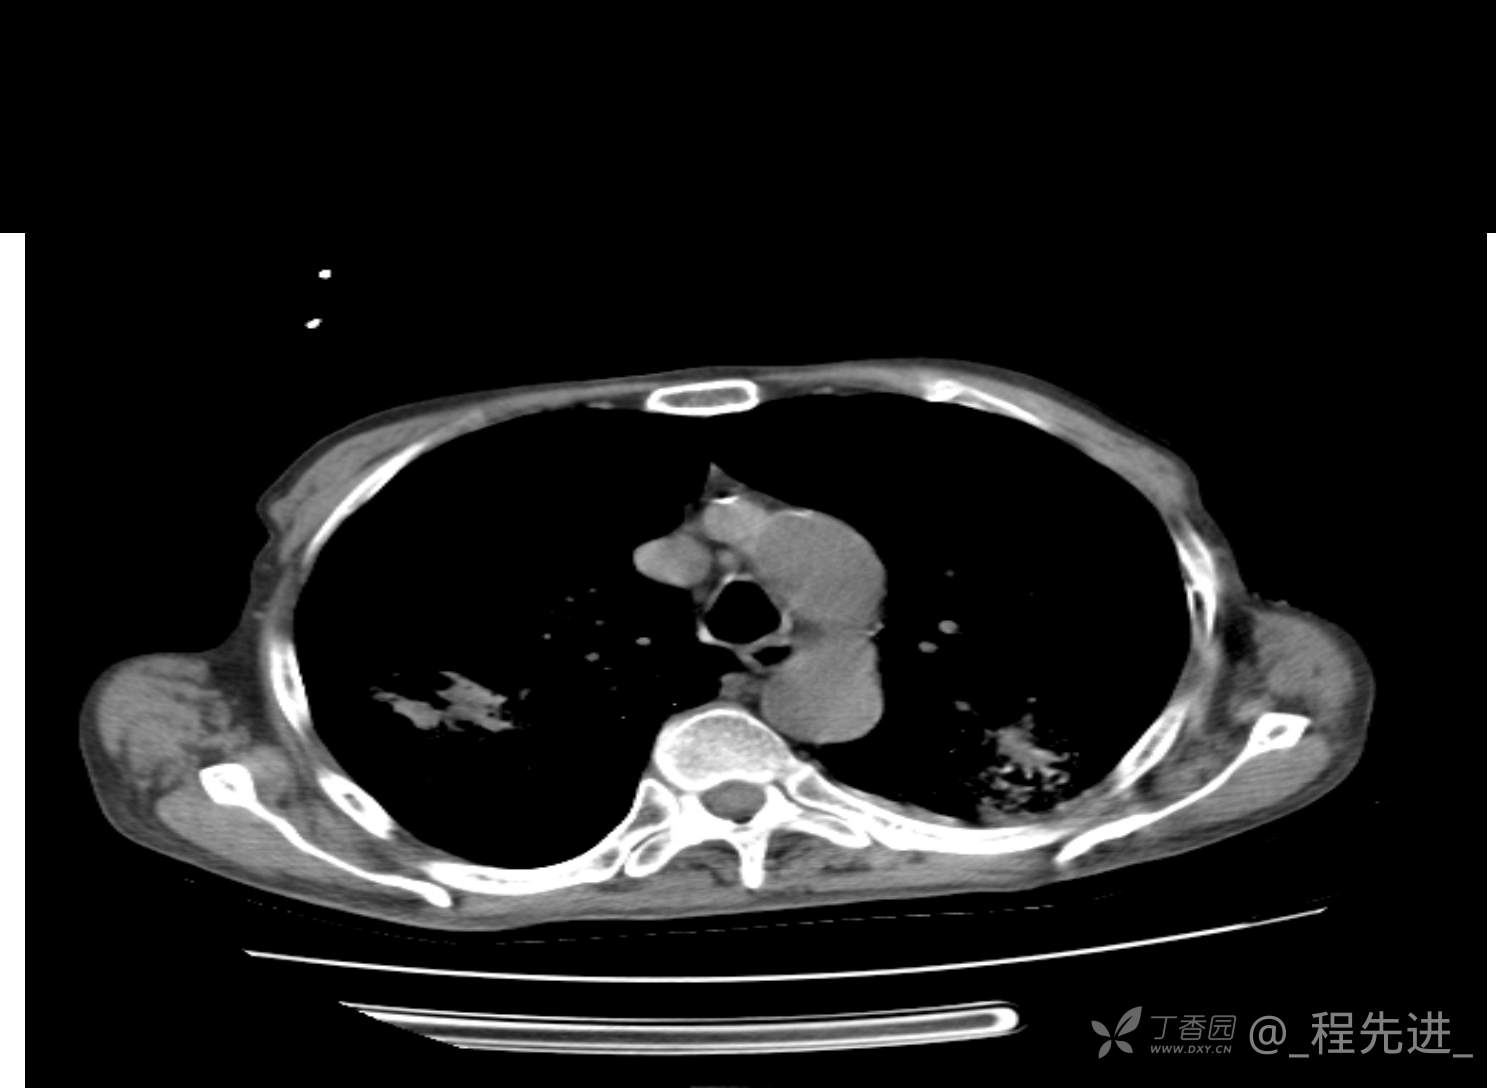

患者性别:男

患者年龄:81岁

简要病史:反复咳嗽、咳痰20余年,加重1周。两肺呼吸音低,可闻及散在干湿啰音。